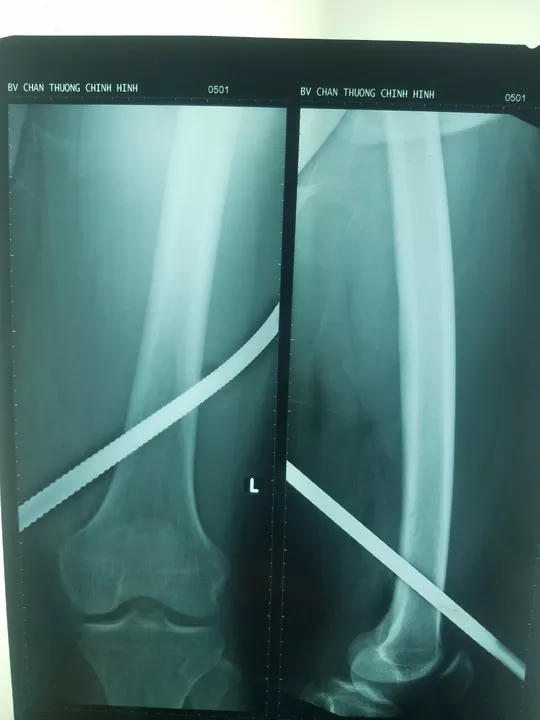

Sáng 17/6, Bệnh viện Chấn thương Chỉnh hình TP HCM cho biết bệnh viện vừa phẫu thuật cấp cứu một nam công nhân xây dựng bị tai nạn lao động. Nạn nhân là anh Trần Văn V (36 tuổi, ngụ quận 8, TP HCM) bị một thanh sắt dài đâm xuyên đùi.

Bệnh nhân kể lại, lúc 10h sáng (ngày 15/6), đang đứng làm việc trên cao 5 mét tại công trường xây dựng ở Q.Tân Bình thì trượt chân té xuống đất. Dưới mặt đất có nhiều thanh sắt dựng thẳng đứng dài 1 mét. Bệnh nhân bị một thanh sắt đâm xuyên qua đùi trái, chân dính chặt vào thanh sắt.

Người nhà phải cắt ngắn thanh sắt rồi chuyển bệnh nhân vào cấp cứu tại Bệnh viện Chấn thương Chỉnh hình

Ngay lập tức, ê kíp phẫu thuật gồm TS-BS Mai Trọng Tường, ThS-BS Nguyễn Ngọc Thạch đã tiến hành mổ cấp cứu thám sát mạch máu đùi, cắt lọc làm sạch vết thương, xử lý tổn thương các động mạch đùi, khoeo, rút được thanh sắt ra ngoài cứu được chân cho nạn nhân.